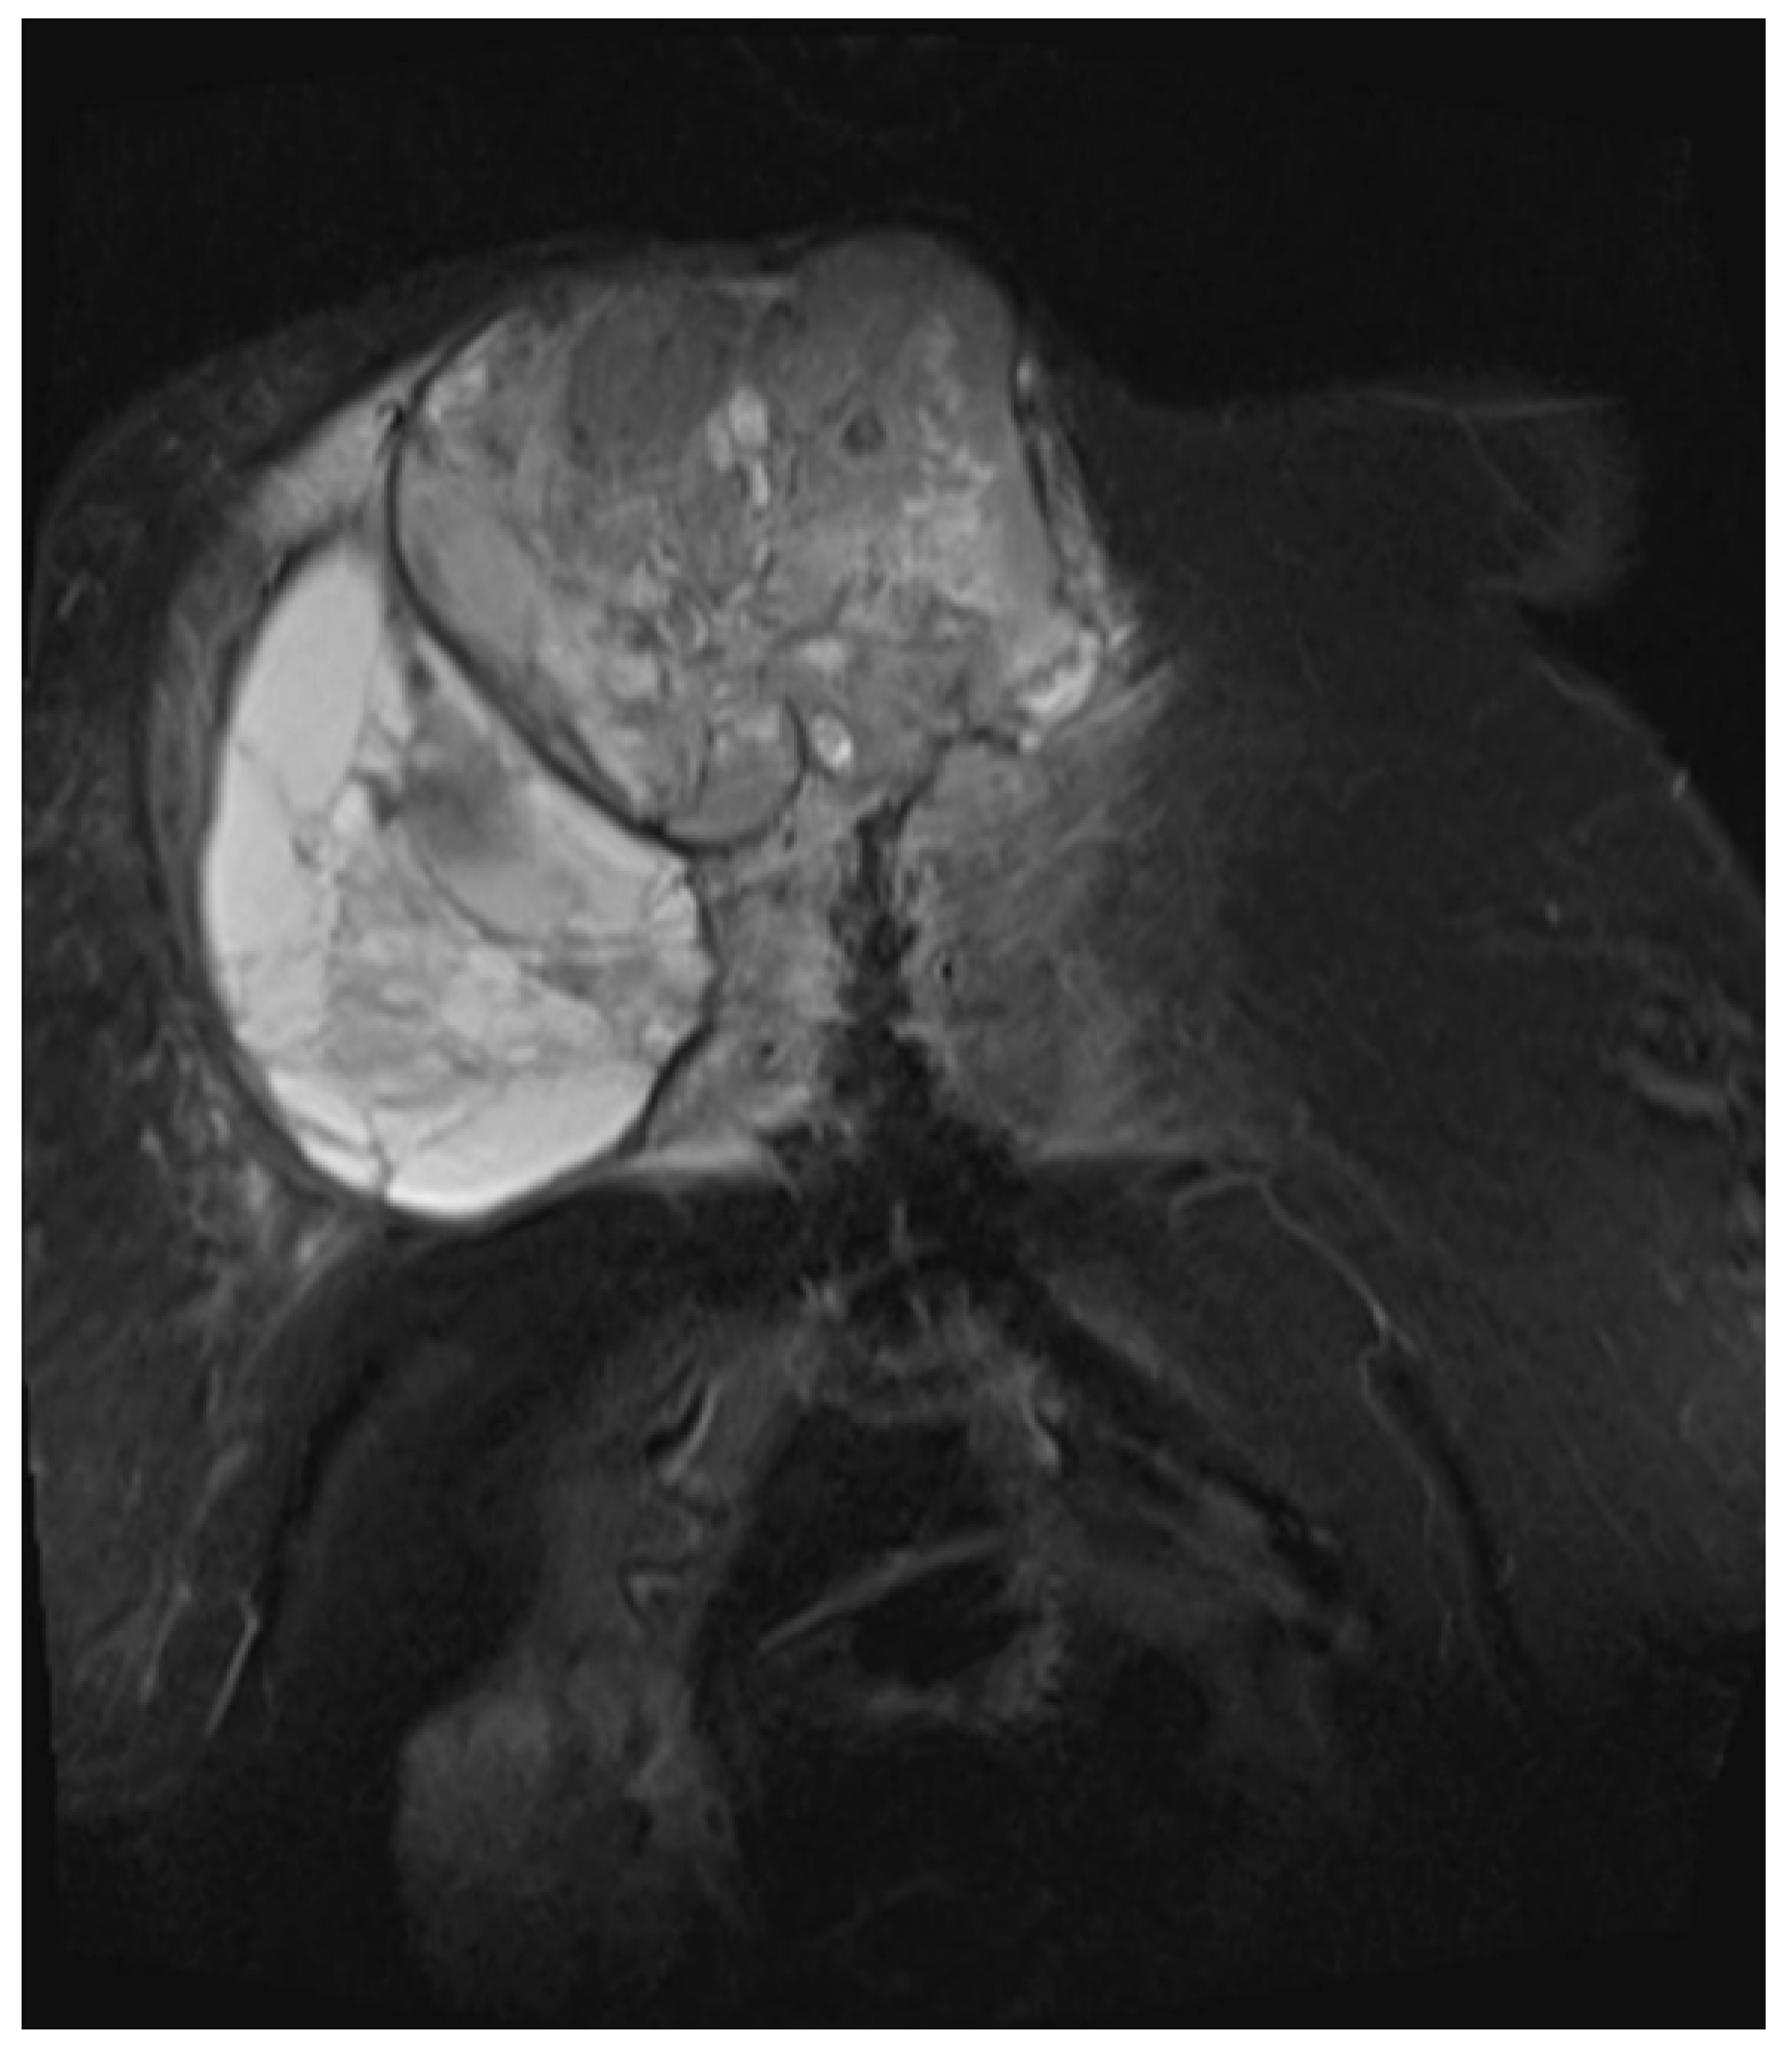

She returned to Bochum in June 2018 with the following symptoms: on the right ventral chest wall, she had a large tumor with a perforation in the pericardium of approximately 15 × 20 cm, an abdominal inguinal tumor on the right, and an ulcerating tumor on the lower left side of the abdomen. A computed tomography of the thorax and abdomen was performed in 09/2018 (Figure 2 and Figure 3) and a magnetic resonance imaging of the thorax was performed in 06/2018 (Figure 4 and Figure 5).

Figure 5.

Magnetic resonance imaging (MRI 2018) showing the bis soft tissue structure, partially calcified and infiltrating the sternum.